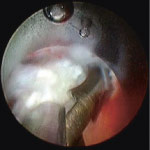

Abb. 1

Über einen kleinen Hautschnitt wird das Instrumentarium bis zum Bandscheibenvorfall vorgeschoben.

Der endoskopische, mikrochirurgische Eingriff erfolgt in Bauchlage. Unter Röntgenkontrolle wird der 5 bis 6 mm kurze Hautschnitt an der rechten Flanke ausgeführt. Anschliessend wird das sehr feine Instrumentarium – ein Endoskop, das den Vorfall sichtbar macht und eine kleine Zange, um das Bandscheibenmaterial zu entfernen, und ein Spülkanal enthält – durch den Hautschnitt eingeführt. Das gesamte Instrumentarium befindet sich in einem schmalen Rohr, das gleichzeitig den Arbeitskanal bildet. Unter Röntgenkontrolle wird dieses seitlich an den Bandscheibenvorfall herangeführt und schrittweise bis auf 7mm aufgedehnt (Abb. 1). Einer der wesentlichen Vorteile des seitlichen Zugangs ist, dass auf dem Weg durch die Muskulatur hin zur Bandscheibe nur sehr wenig Gewebe und keine knöchernen Strukturen verletzt bzw. eröffnet werden. Voraussetzung für die Anwendung dieser Technik ist die Lokalisation des Bandscheibenvorfalls auf der Seite und nicht im Bereich des zentralen Spinalkanals, wo sich eher offene Eingriffe empfehlen.